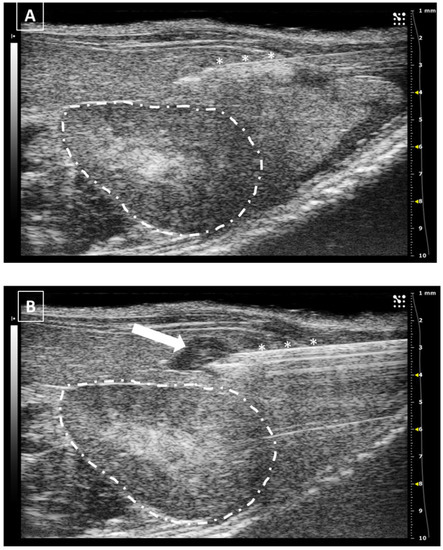

For pancreatic injections, frequently performed in oncology for developing pancreatic tumors, the best area for injecting is the left branch. The middle one is smaller and the right branch is more complicated to access due to the presence of the duodenum and the right kidney. For injecting in the left branch, we need to localize the primary splenic vein that runs cranially to the cranial pole of the left kidney, from its origin in the spleen to its insertion in the cava vein. The pancreatic area can be recognized as a poorly defined isoechoic area with internal parallel hyperechoic lines around the vein. In this place, the needle can be introduced from the lateral side while we keep the scanning probe in a medial position. In a standardized image, the needle will appear from the right side of the screen. As happens with other lateral approaches, sometimes we will need to make some pressure from the contralateral side of the animal to overcome the skin and abdominal wall resistance to the puncture. Once these two structures are pierced, the injection can be performed without difficulties. A small anechoic bubble arising in the pancreatic area can be observed if the injection is performed correctly. We should wait a few seconds before removing the needle as we do in other procedures. An example of a pancreatic injection is displayed in Figure 6.

The major risk of this injection will not affect the health of the animal but the success of the model. Several times we can observe, after the injection, that the fluid from the syringe is not creating an anechoic bubble but moving freely to the ventral wall of the abdomen (the top of the monitor because we positioned the animal in ventral recumbency). This happens when the injection is not correctly performed in the pancreatic tissue but in the peritoneum. In this situation, we should stop injecting and relocate the tip of the needle to another area. Otherwise, we will have an abdominal disseminated model of pancreatic tumors.

There is no limitation on the volume injected in the pancreas due to the minimum stiffness of the tissue, but in most of the publications, the injected volume range goes from 20 to 50 microliters [32,33,34].

Figure 6. Intrapancreatic injection. (A) The needle is marked with white asterisks and injected in the pancreatic area. The left kidney is surrounded with a dashed line. (B) Same area after injection. The fluid collection is signaled with a white arrow. Images obtained at 40 MHz frequency.